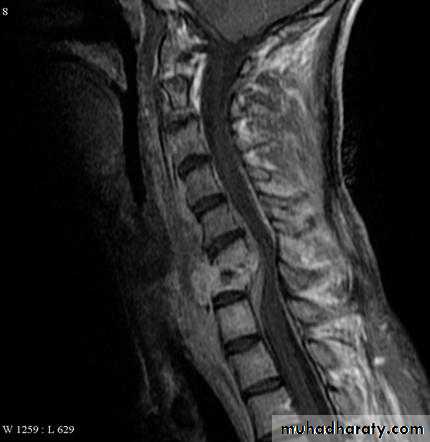

Chronic retropharyngeal abscess

Aetiology: tuberculosis

X-ray of cx. Spine shows sign of tuberculosis

.